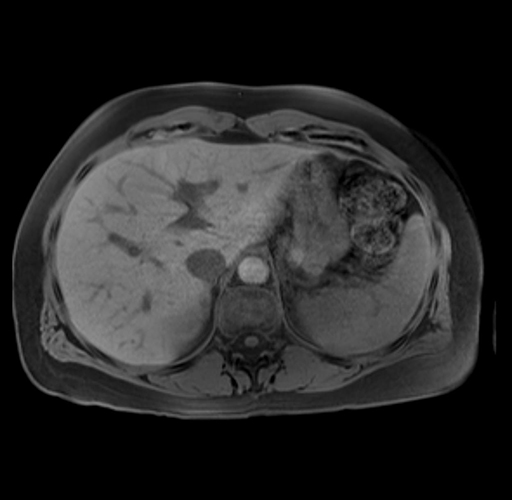

Imaging Analysis

Look through the patient's CT scan to identify any areas of concern for the necessary procedure.

Based on your CT findings, which issue(s) are present and would give reason for "planned slowing down moment(s)" in this case?

Considering a standard distal pancreatectomy procedure, what step(s) of the operation would you do differently in this case?